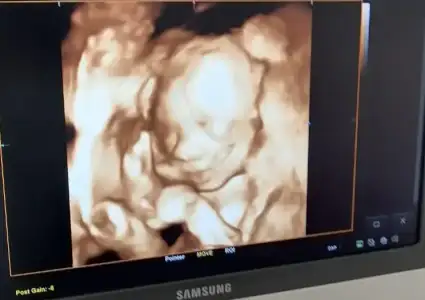

Çarşamba günü şeker yüklemesi yapıldı. Çok fazla kan aldılar. Bundan dolayı çok yorgundum halsiz kaldım. Şükür Sonuçlar iyi çıktı kadın doğum Doktorum da muayene mi yaptı, oğlumu gördüm ilk defa bize yüzünü gösterdi. Babasından, annesinden, ablasından üçümüz den de bir şeyler almış. Onu görmek çok güzel bir duyguydu. 800 gr olmuş iri olacak dedi. Rabbım sağlıkla kucağıma almayı nasip et.